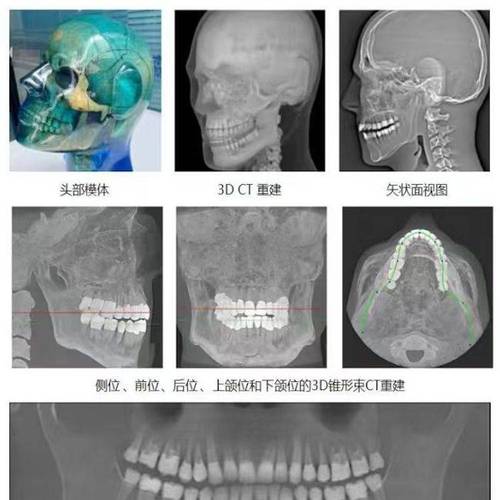

头颅侧位片的分析涵盖骨骼、牙齿、软组织三大维度,通过一系列标志点和测量参数实现量化评估,以下是关键指标及其临床意义:

骨骼分析指标

骨骼分析主要评估颅骨、上颌骨、下颌骨的相对位置及生长发育趋势,核心标志点包括蝶鞍中心(S)、鼻根点(N)、上齿槽座点(A)、下齿槽座点(B)、颏前点(Pg)等。

牙齿分析指标

牙齿分析聚焦牙齿排列、倾斜度及位置关系,标志点包括上中切牙切缘(U1)、下中切牙切缘(L1)、上颌第一磨牙近中接触点(U6)、下颌第一磨牙近中接触点(L6)等。

软组织分析指标

软组织分析关注面部美学协调性,标志点包括鼻尖点(Prn)、上唇突点(Ls)、下唇突点(Li)、颏下点(Snog)等。

头颅侧位片在矫正中的核心应用